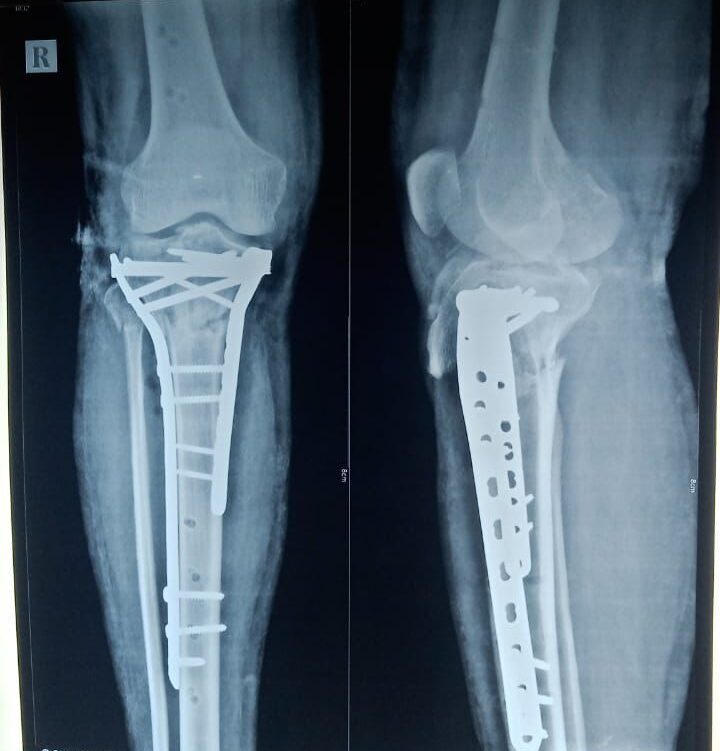

Moments That Mark Meaningful Recovery

Witness real patient transformations at The Ortho Clinic through images that reflect successful treatments and restored mobility.